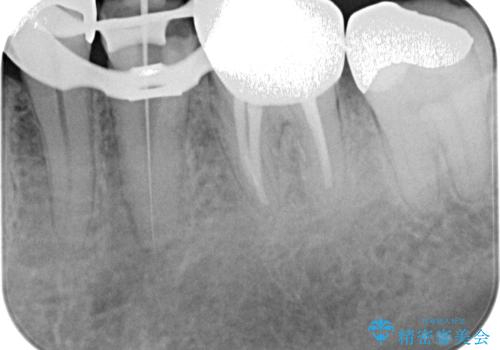

- 近医にてむし歯治療として根管治療を受けるも、痛みが全く改善しないとのことで来院された患者様です。

痛みが継続するため、「根管治療」と検索したところ、「ラバーダム」の重要性を知るところとなったようです。

根管治療を実施した後に、フルジルコニアクラウンにて補綴することとしました。

奥歯に痛みがあるとのことで診察を行ったところ、海外(アメリカ)にて処置をした手前の歯が既に失活していることが分かりました。なお、治療を行った大臼歯はレントゲン写真上の治癒が認められました。